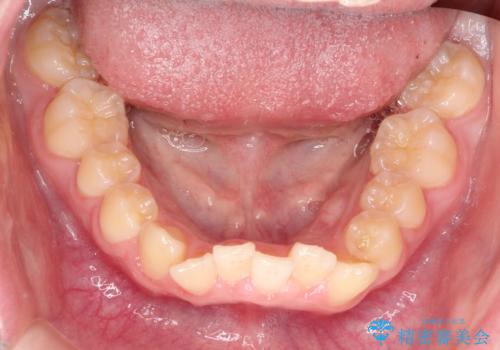

上下の前歯のガタガタを目立たず治したい インビザラインによる見えない矯正

- 上下の前歯のガタガタを治したいとのことで来院されました。

上下の歯と歯の間をわずかに削り、並べる計画としました。